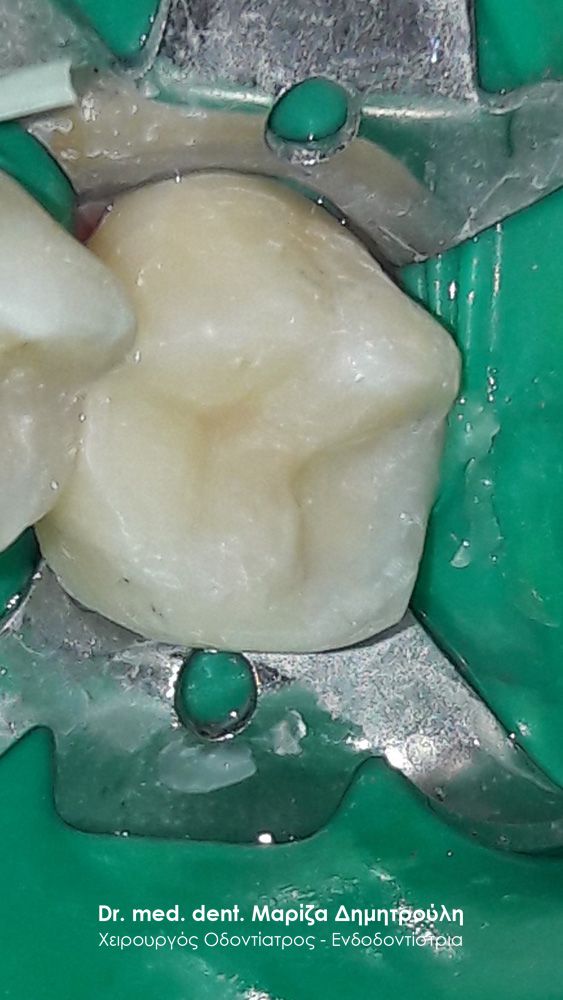

Περιστατικό – Αντικατάσταση σφραγισμάτων δοντιών

Ο ασθενής επιθυμούσε την αντικατάσταση των παλιών μαύρων σφραγισμάτων αμαλγάματος με λευκά σφραγίσματα σύνθετης ρητίνης.

Η θεραπεία πραγματοποιήθηκε με τη χρήση ελαστικού απομονωτήρα, όπως ορίζουν τα παγκόσμια πρωτόκολλα οδοντιατρικής για την αφαίρεση των μαύρων σφραγισμάτων. Οι οδοντίατροι θα ήταν καλό να χρησιμοποιούν απομονωτήτρα κατά την αφαίρεση σφραγισμάτων αμαλγάματος, έτσι ώστε ο ασθενής να εισπνέει ελάχιστα και να μην καταπίνει τον υδράργυρο, που απελευθερώνεται κατά τη διαδικασία αυτή.

Το σχέδιο θεραπείας του πρώτου γομφίου (δόντι με πολύ λευκό σφράγισμα) ήταν υπό συζήτηση, γι΄ αυτό και η αποκατάσταση του δοντιού με προσωρινό σφράγισμα.

ΠΡΙΝ

META